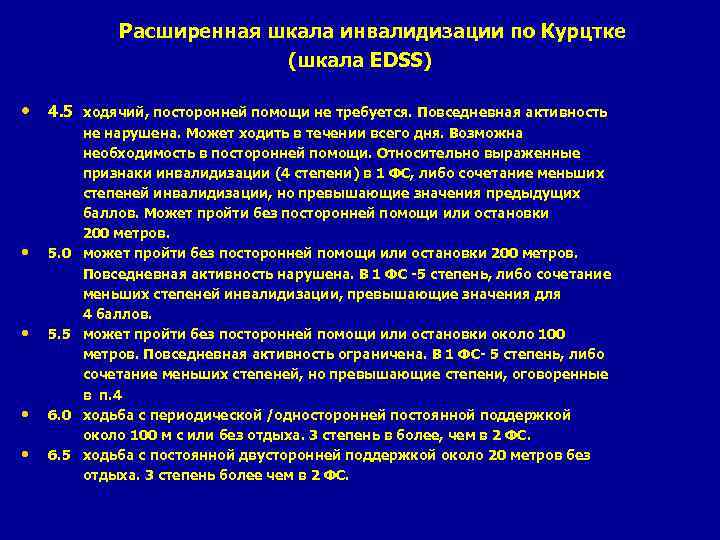

Расширенная шкала инвалидизации по Курцтке (шкала EDSS) • 4. 5 ходячий, посторонней помощи не требуется. Повседневная активность не нарушена. Может ходить в течении всего дня. Возможна необходимость в посторонней помощи. Относительно выраженные признаки инвалидизации (4 степени) в 1 ФС, либо сочетание меньших степеней инвалидизации, но превышающие значения предыдущих баллов. Может пройти без посторонней помощи или остановки 200 метров. • 5. 0 может пройти без посторонней помощи или остановки 200 метров. Повседневная активность нарушена. В 1 ФС -5 степень, либо сочетание меньших степеней инвалидизации, превышающие значения для 4 баллов. • 5. 5 может пройти без посторонней помощи или остановки около 100 метров. Повседневная активность ограничена. В 1 ФС- 5 степень, либо сочетание меньших степеней, но превышающие степени, оговоренные в п. 4 • 6. 0 ходьба с периодической /односторонней постоянной поддержкой около 100 м с или без отдыха. 3 степень в более, чем в 2 ФС. • 6. 5 ходьба с постоянной двусторонней поддержкой около 20 метров без отдыха. 3 степень более чем в 2 ФС.